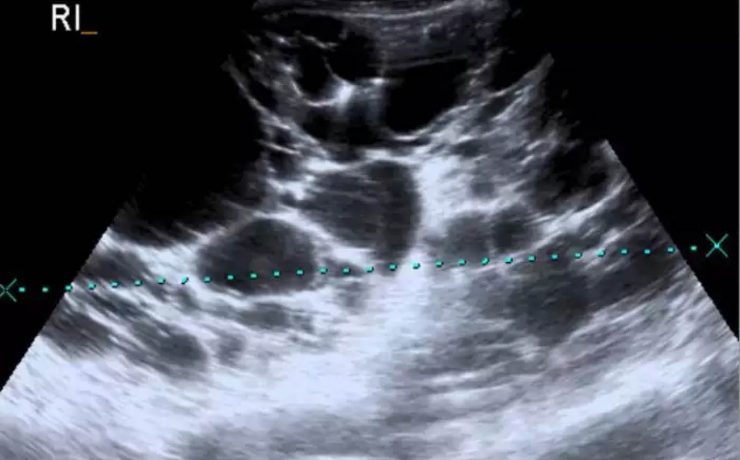

Patologías benignas de la próstata: prostatitis e hiperplasia benigna

En este estudio se llevó a cabo un análisis de la anatomía prostática; los factores más relevantes que regulan el crecimiento prostático y y las funciones de la glándula que podrían influir en la etiología de diferentes patologías de la próstata; parámetros claves en el diagnóstico temprano y de estas